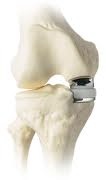

Model of partial knee replacement

Labelled diagram of uni knee replacement